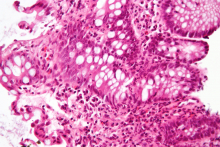

School of Biological Sciences Patton Professor Greg Gibson joins Emory colleague in addressing the need for more diverse genetic risk assessments — conducting the largest genome sequencing yet for African-Americans with IBD and Crohn's disease.